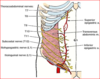

Peri-nephric abscess

spread to pelvis due to fascial attachment

- DOES NOT SPREAD TO ADJ KIDNEY

causes:

- UTI

- staph aureus

- DM

- lsions of urinary tract: stones, cyst